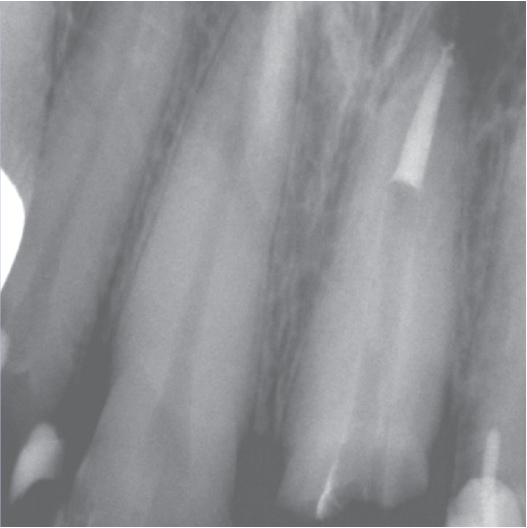

Before

Before Root Canal treatment